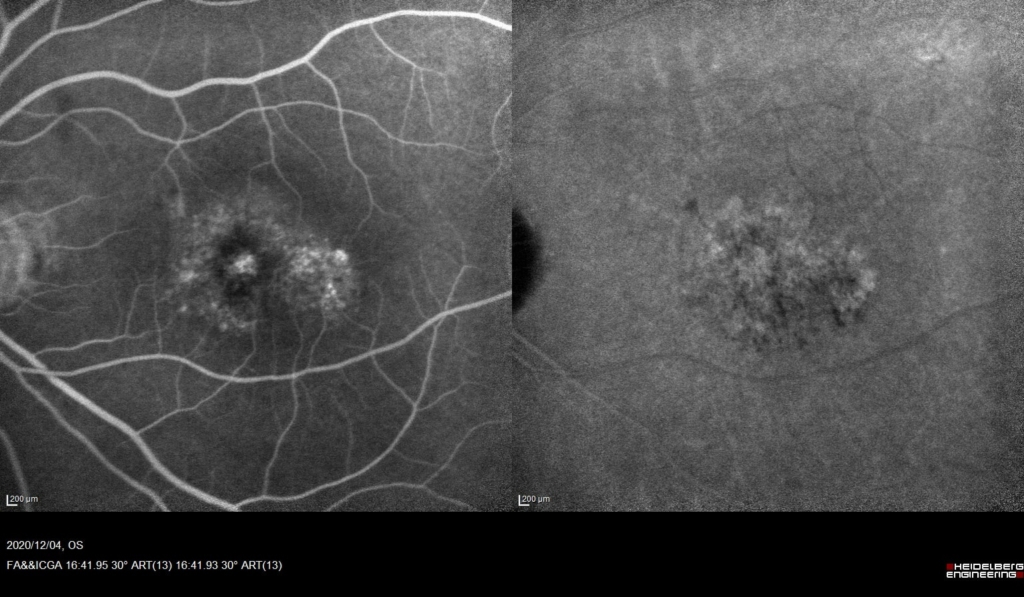

黄斑に、IAでCNVの網目状の血管がみられる。

FAでびまん性に漏出がみられる。